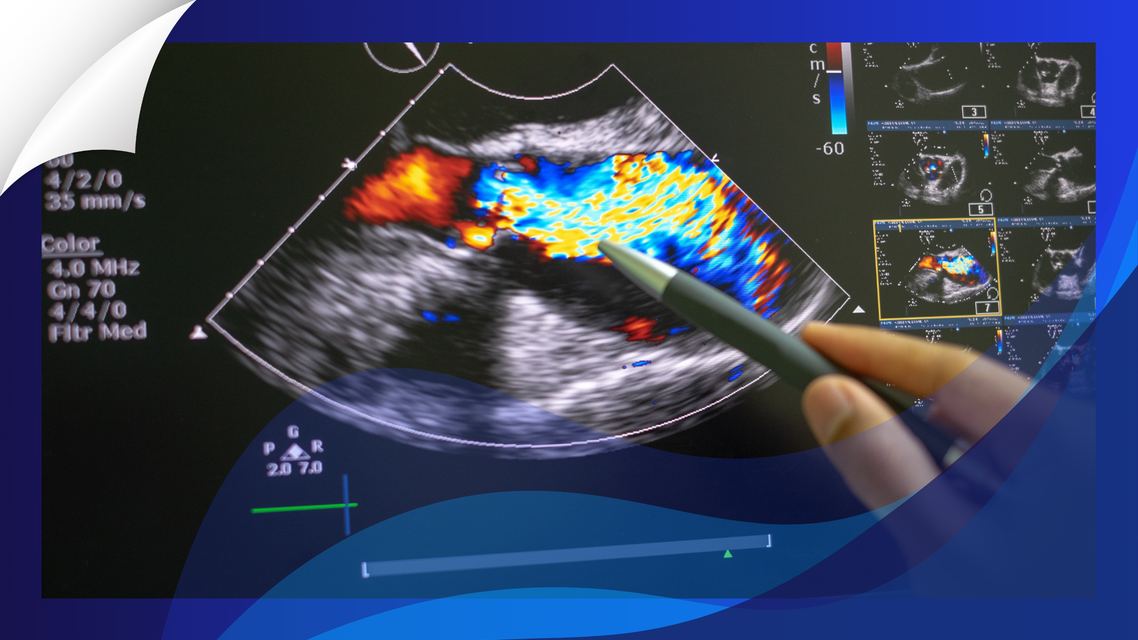

In a comprehensive multimodality imaging study, Ozbay and colleagues provide compelling evidence that the left atrium itself is intrinsically diseased in ATTR-CM—and that this primary atrial cardiopathy independently contributes to thrombotic risk.

In a propensity-matched cohort of 104 patients with ATTR-CM and 104 patients with non-amyloid left ventricular hypertrophy (LVH), the atrial phenotype diverged in clinically meaningful ways. Left atrial reservoir strain (LASr) was markedly reduced in ATTR-CM (approximately 10% vs 17% in LVH), while left atrial stiffness was more than doubled (median ~2.1 vs 0.9 1/%). These abnormalities were present despite smaller or only mildly enlarged left atrial volumes in ATTR-CM.

Unlike the LVH cohort, atrial size in ATTR-CM did not increase proportionally with worsening diastolic dysfunction and showed poor correlation with filling pressures or strain parameters. This dissociation between chamber size and mechanical function supports the concept of direct amyloid infiltration producing structural and electromechanical impairment rather than secondary remodeling from pressure overload alone.

Cardiac magnetic resonance further reinforced this distinction; atrial late gadolinium enhancement (LGE) was more intense in ATTR-CM, yet mechanical dysfunction was already severe even at lower LGE grades, suggesting a diffuse infiltrative substrate rather than a purely fibrosis-mediated process.

Instead, mechanical parameters carried prognostic weight. An LASr threshold of 9% or lower was associated with a 7.8-fold increased risk of thrombotic events after adjustment for atrial fibrillation. An atrial stiffness value of 1.7 or greater conferred roughly a fourfold increased risk. Left atrial volume index did not predict events, reinforcing that deformation and stiffness—not size—capture the clinically relevant substrate.